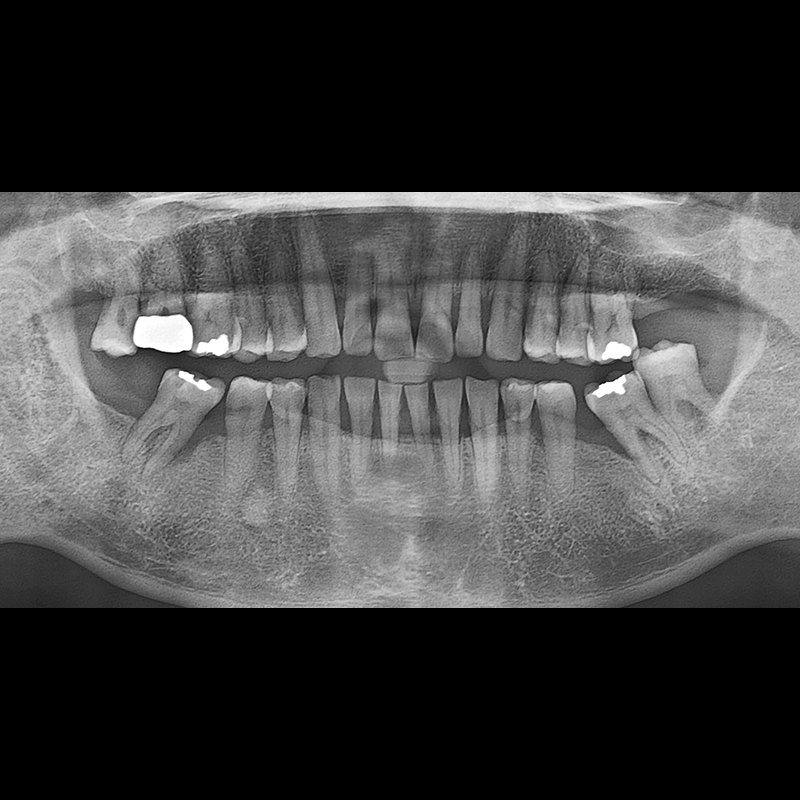

BEFORE AFTER

インプラント手術事例 2025.05.30

欠損した歯の部分と、生かしにくい歯の位置にインプラントを植立しました。